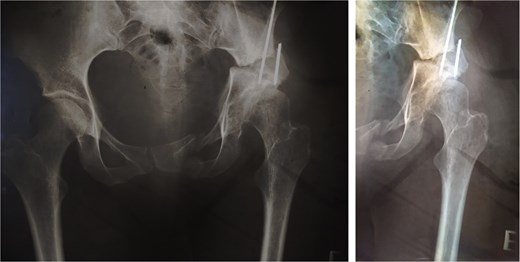

Twenty-eight years after triple osteotomy, the patient presented with painful end-stage osteoarthritis, with body mass index of 18. A hybrid cemented THA was performed using a standard posterolateral approach (Fig. 3). A cobalt-chrome femoral head was articulated with highly reticulated polyethylene liner. A press-fit cementless cup stabilized with two screws (Tylogy®, Zimmer) and a cemented straight femoral stem (Müller®, Zimmer) were implanted.

Anteroposterior radiographs of the pelvis 28 years after the pelvic osteotomy, showing advanced left hip osteoarthritis (Tönnis Grade V). A hybrid cemented total hip arthroplasty was implanted using a standard posterolateral approach.